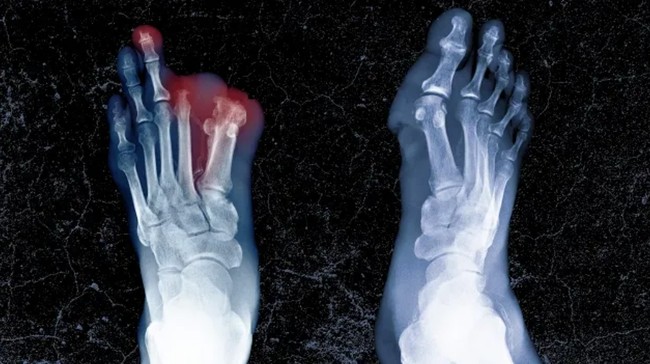

Bakteri yang diduga datang dari makanan sisa temannya didiagnosa telah menyebar. Bahkan jari kaki hingga sebagian kakinya harus diamputasi demi menyelamatkan nyawanya.

Ternyata kebiasaan buruknya itu memicu terjadinya diabetes tipe 2 pada tubuhnya. Bertahun-tahun lamanya ia harus melawan diabetes yang membuat luka pada kakinya membusuk.

Sampai-sampai ia harus merelakan kakinya diamputasi. Kini wanita tersebut hanya mengandalkan kursi roda dalam berbagai aktivitas kesehariannya.